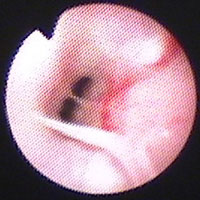

鼻腔鏡検査:気管支鏡検査と同時に行った。retroflex法により鼻咽頭を観察した。粘膜は充血発赤し、粘稠分泌物がみられた(図12)。ブラシ擦過標本の細胞診にて大小リンパ球および形質細胞が多数みられ(図11右)、培養では陰性であった。

図12 症例3の鼻腔鏡検査所見。粘膜は充血発赤し、粘稠分泌物がみられた。